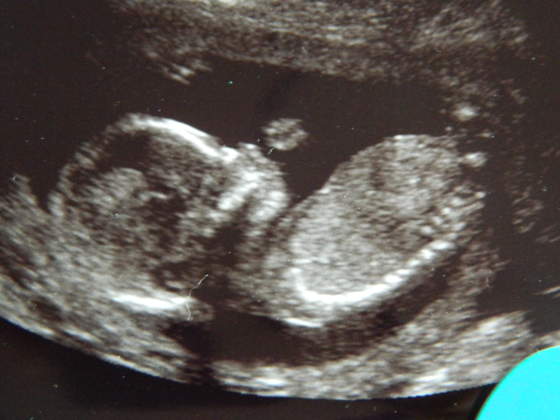

Kruszki, piękne zdjęciaA znacie płeć? Bo mi na dziewczynkę wygląda - tak po twarzy

hehehe no to zescie teraz napisalykruszki piękne małe słoneczko, a mnie na chłopczyka wyglądahihi

...w końcu dowiemy się wszystkie kto mieszka w naszych brzuchach... :-)